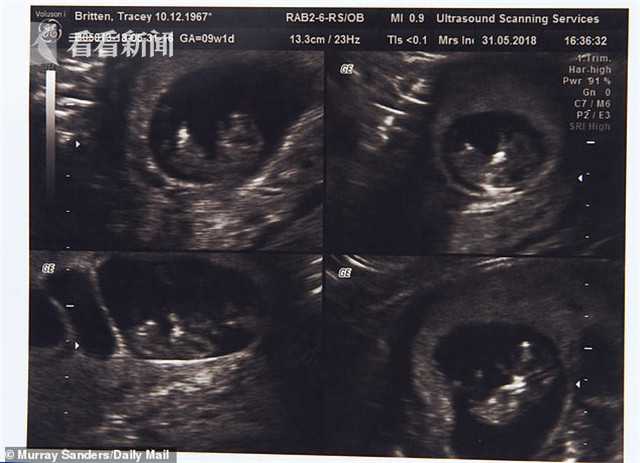

50歲時(shí),特蕾西與丈夫斯蒂芬花了7000英鎊(約合人民幣62317元)在塞浦路斯通過(guò)試管嬰兒手術(shù),懷上了四胞胎,其中三個(gè)是女孩,一個(gè)是男孩,三個(gè)女孩中還有一對(duì)是同卵雙胞胎。